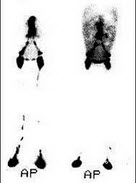

8、多项选择题

女,35岁,发现颈部包块就诊,行TcO甲状腺显像如图,可能的诊断为()

A.Plummer病

B.此结节为“热结节”

C.甲状腺功能亢进

D.桥本氏病

E.甲状腺癌

点击查看答案